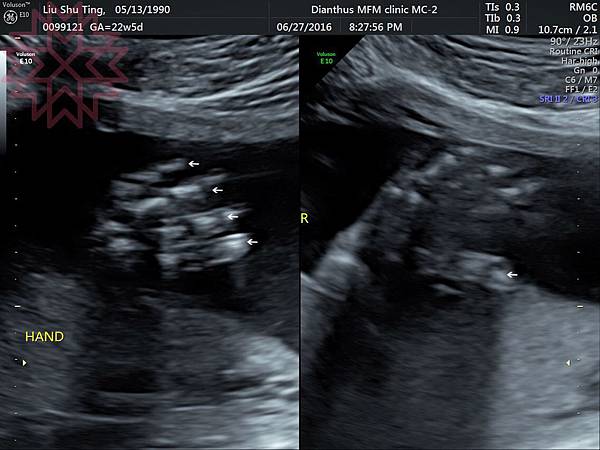

這就是讓我們數的很辛苦的腳ㄚ子~

這是兩邊的小手~~